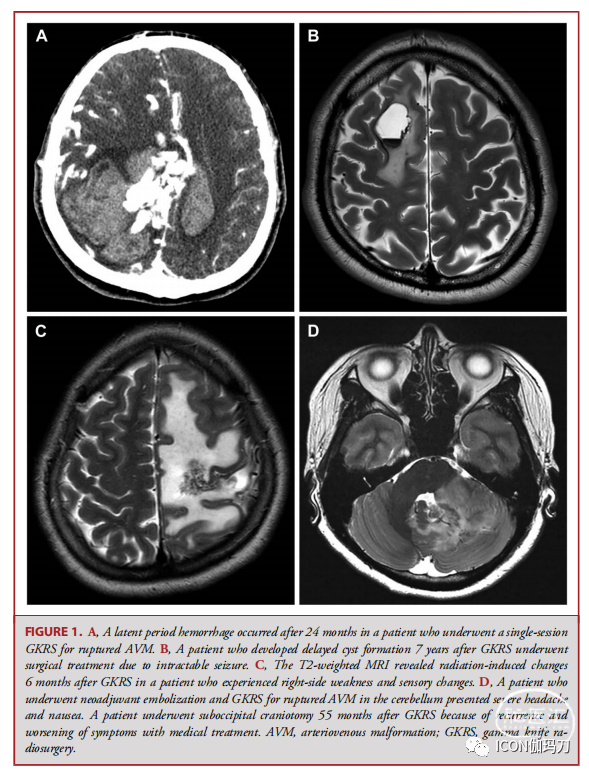

147例患者(64.5%)实现了血管闭塞,其中6例(2.6%)出现潜伏期出血(图1A), 9例(3.9%)出现囊肿形成(图1B), 97例(42.5%)出现RICs(图1C),其中64例(66.0%)被分类为无症状,24例(24.7%)有一过性症状,经药物治疗和观察后可逆;9例(9.3%)为GKRS治疗后永久性RICs(表1)。2例发生隐性出血的患者因意识改变接受了手术治疗,2例发生迟发性囊肿的患者因难治性癫痫接受了囊肿切除术。4例永久性RICs患者加重了放射性坏死(图1D),并接受了手术治疗(2例重度头痛;2难治性癫痫发作)。新辅助栓塞组16例患者(55.2%)、辅助栓塞组9例患者(47.4%)和非栓塞组122例患者(67.8%)。在GKRS治疗后达到了MRI/MRA或血管造影闭塞(表2)。根据Fisher精确检验(P = 0.1119)(表2),差异无显著性。图2B)、延迟形成的囊肿(P = 0.880;图2C)和RICs (P = .297;图2D)无显著组间差异。

图1。A,一名因AVM破裂接受单次GKRS治疗的患者在24个月后发生了潜伏期出血。B: GKRS治疗后7年出现迟发性囊肿,因难治性癫痫行手术治疗。C, T2加权MRI显示GKRS治疗后6个月的放射性改变,患者出现右侧无力和感觉改变。D, 1例因小脑动静脉畸形破裂接受新辅助栓塞联合GKRS治疗的患者出现严重头痛和恶心。1例GKRS治疗后55个月因药物治疗后症状复发、加重行经枕下开颅手术。AVM,动静脉畸形;GKRS,伽玛刀放射外科